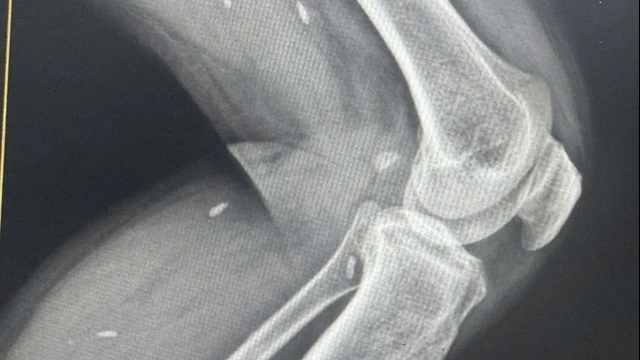

Theo lãnh đạo Bệnh viện Đa khoa Trung ương Quảng Nam thông tin, hiện có 17 trường hợp trong vụ tai nạn này điều trị tại bệnh viện; trong đó, 3 trường hợp nặng nhất đã được thực hiện các phẫu thuật… Tình hình sức khỏe các nạn nhân đều ổn và bệnh viện sẽ tiếp tục theo dõi kỹ lưỡng, tránh bỏ sót các chấn thương nhỏ ảnh hưởng đến người bệnh.